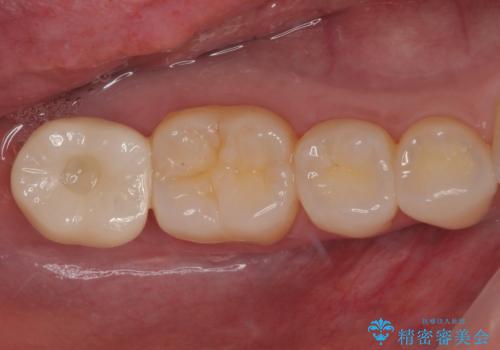

最新の症例

Latest cases